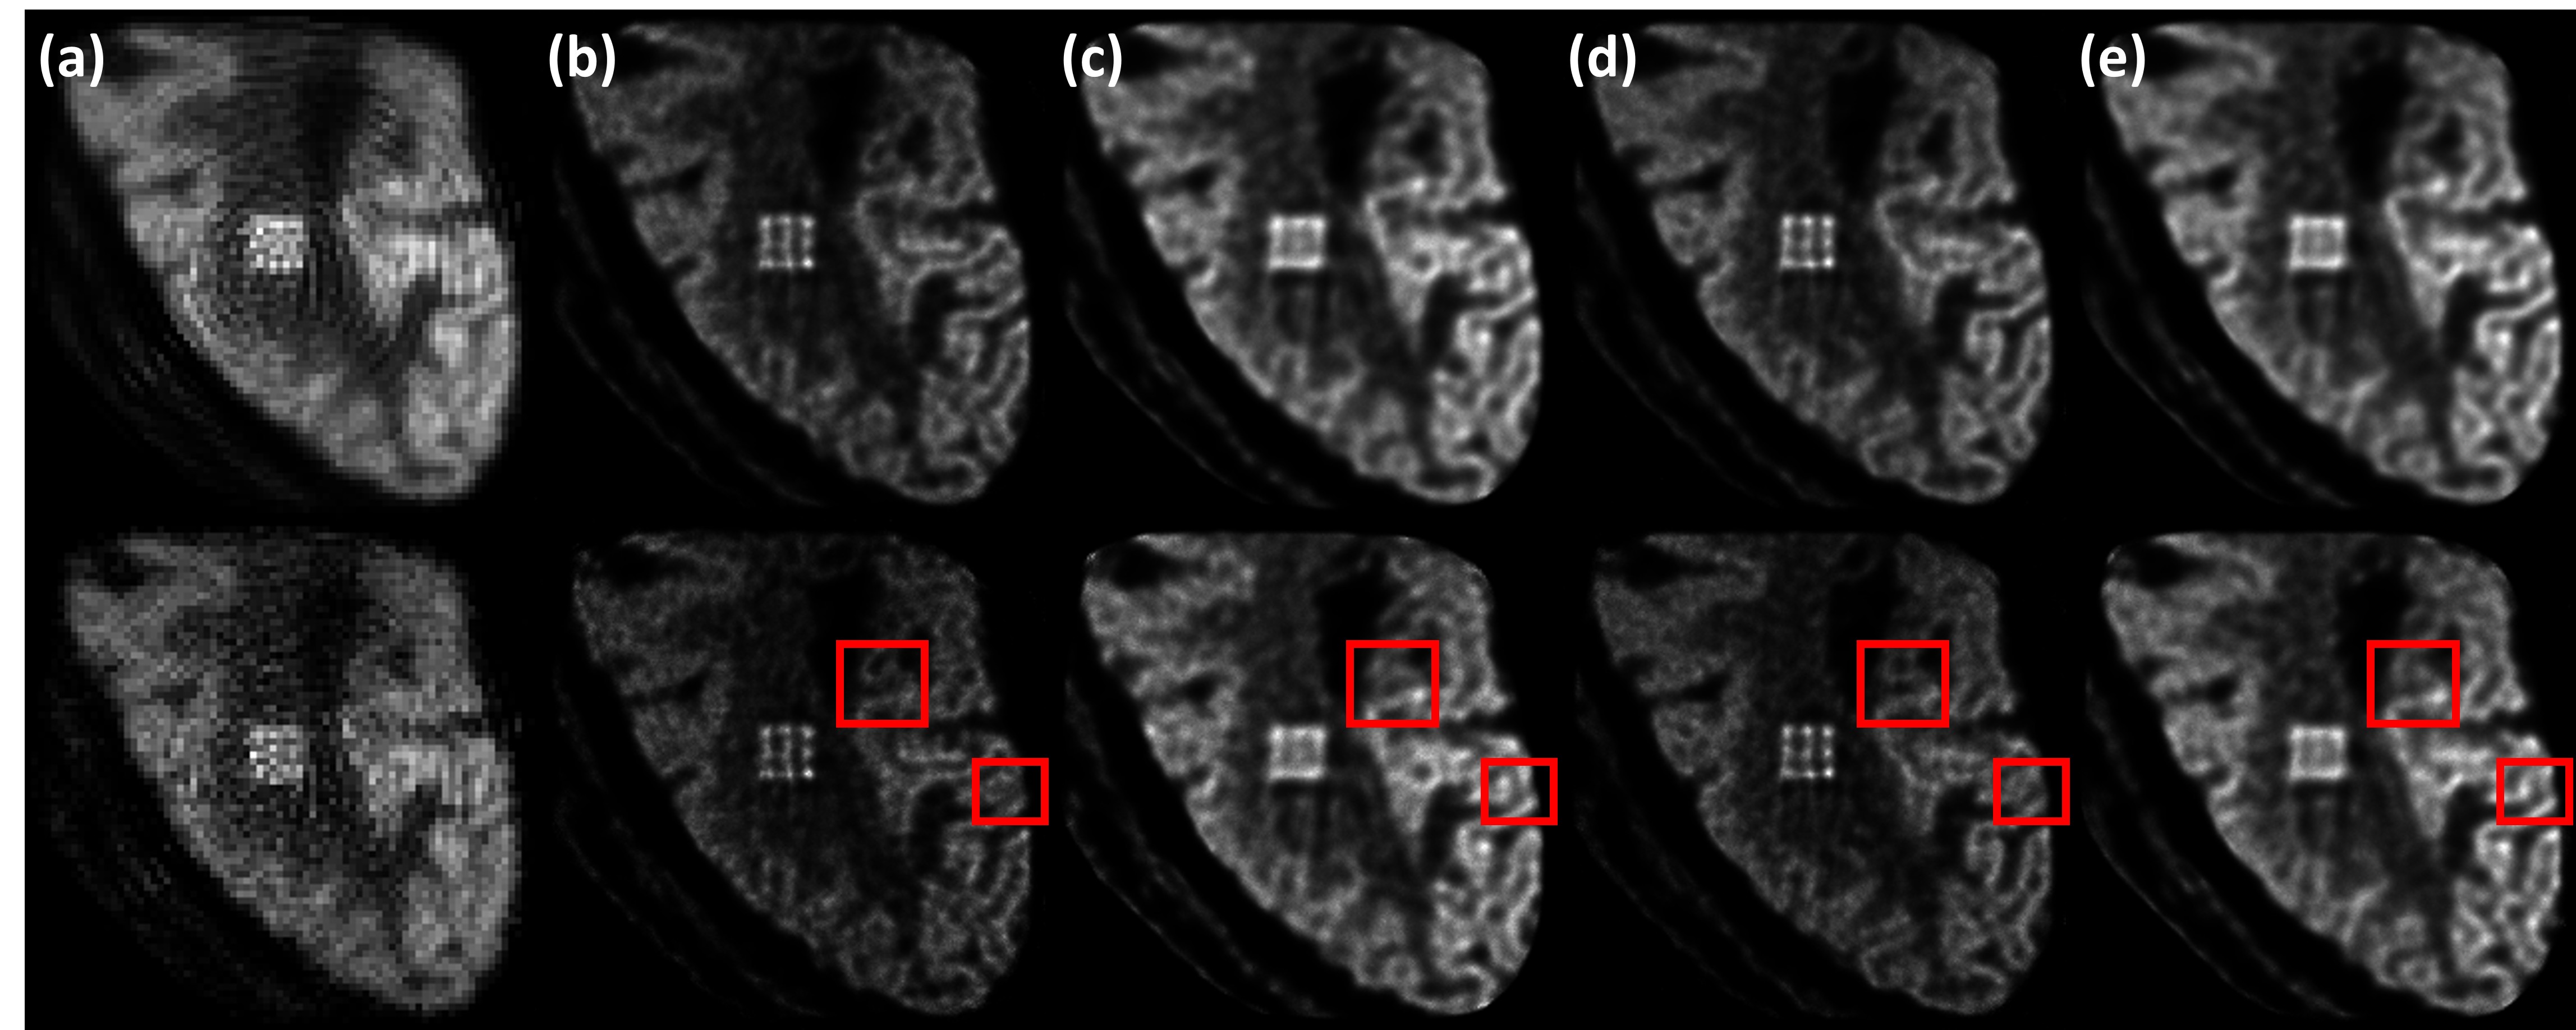

Figure 12: S (a), M2 (b,d), and M0 (c,e) images of the brain phantom obtained from GATE data. Two datasets corresponding to two different scan durations were produced for the situations when no modulator was used (S and M0) and when the M2 modulator was used. The M2 and M0 data in dataset 1 had 7.7M events (b) and 13.2M events (c), respectively. In dataset 2, they had 13.4M events (d) and 23.0M events (e). The S image used the M0 data in dataset 1. Images in the top (bottom) row were obtained using 25 (50) iterations. Compared to the phantom in figure 2(b), structural errors in the M0 images can be observed (the red rectangles show two examples).

Figure 12 shows the S, M0, and M2 images obtained from GATE data for the brain phantom. As in section 4.4, 1.0 mm pixels were used for S and 0.3 mm pixels were used for M0 and M2. Two datasets simulating different scan durations were produced, yielding 7.7M and 13.2M events for M2 and M0 in dataset 1 and 13.4M and 23.0M events for M2 and M0 in dataset 2. Again, it can be observed that the S image has the lowest spatial resolution and also suffers from ring-like artifacts. Under the same scan duration and OSEM iteration number, even though it had only about 43% fewer events, M2 shows considerably better resolution than M0. For both datasets, the lesions are resolved in M2 but not in M0. Visually, M2 can clearly resolve most gyri while the boundaries are less distinct in M0. Some structural errors also appear in M0.